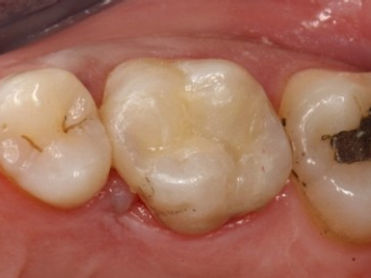

Voici une dent avec une reprise de carie sous un amalgame (appelé aussi plombage) :

Cette reconstitution défectueuse est retirée, et voilà ce qu'il reste de la dent :

Cette dent très abimée est toujours vivante, et les parois restantes sont encore en bon état,

nous pouvons les conserver. Nous allons donc prendre une empreinte de cette cavité pour

faire réaliser par le laboratoire de prothèse un onlay (aussi appelé Inlay) en composite.